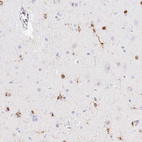

Immunohistochemistry analysis in human lymph node and heart muscle tissues using HPA063903 antibody. Corresponding APBB1IP RNA-seq data are presented for the same tissues.